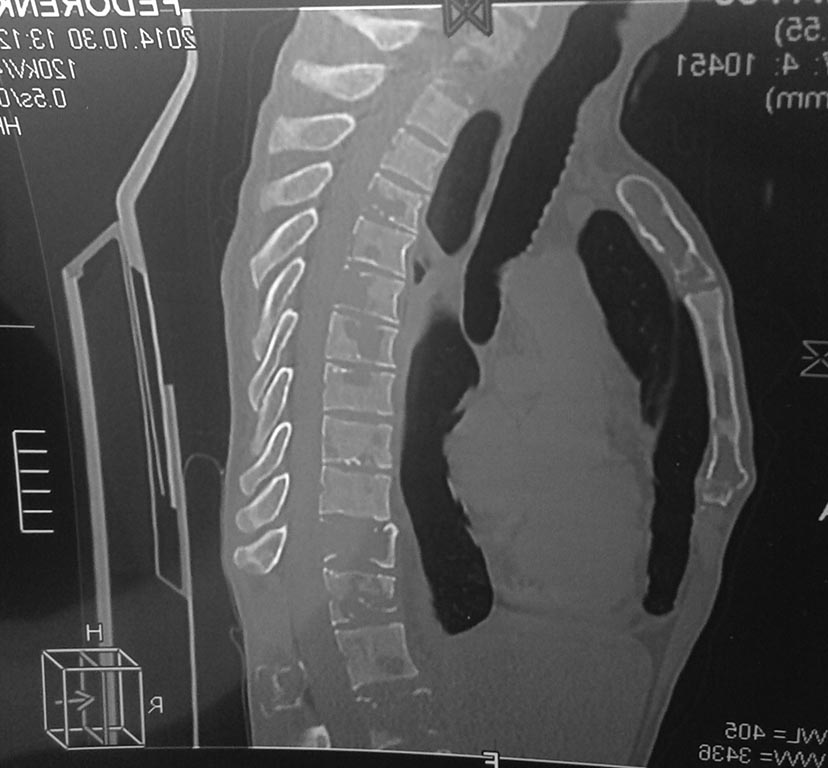

Здравствуйте,Уважаемые коллеги! Пациент М.39лет, работает на разрезе в

Якутии. Первый раз обратился по поводу перелома шейки

бедренной(высокоэнергетическая травма - падение с высоты около 4-х

метров на работе) кости год назад - прооперирован - закрытая репозиция,

остеосинтез 3 винтами. Послеоперационный период без осложнений. Уехал

домой - на контрольных снимках - срослось - пациент доволен результатом

-трудоспособен. Неделю назад со мной связалась его супруга - резкое,

практически молниеносное ухудшение общего состояния, перестал

передвигаться, похудел на 15 кг. Жалобы только на боли в позвоночнике,

нога не беспокоит.В анализах - ни к чему не предерешься. В Якутии

разводят руками. Сразу извиняюсь на скудность и качество снимка - но это

то, что они смогли мне переслать.

Вопрос - миеломная ли это болезнь и куда направить его с данной

патологией - чтоб поближе к месту его жительства. Спасибо.